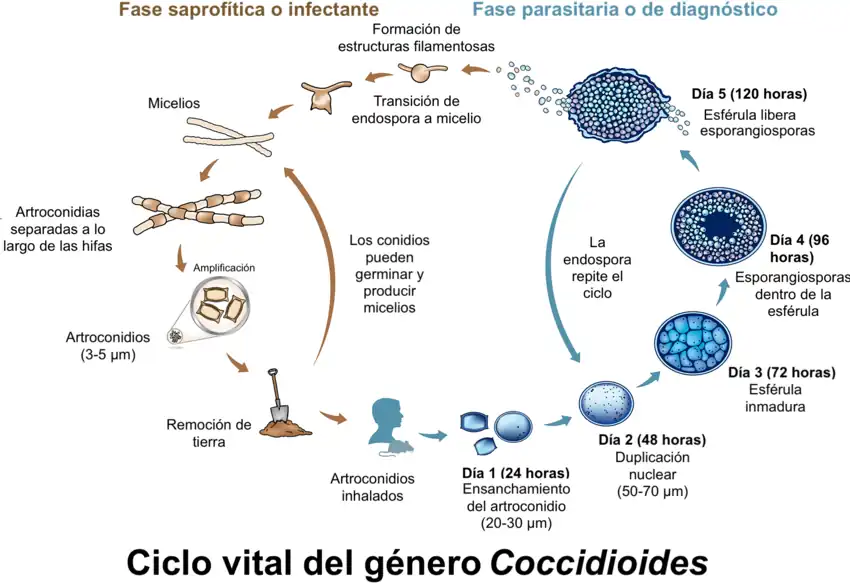

Su forma saprofítica miceliana crece en suelos semidesérticos ricos en sales y materia orgánica de norte, centro y sur del continente americano. El micelio al madurar forma en células alternas artrosporas en forma de tonel, de 3 x 6 μm y pared gruesa, que son las formas infectantes. El cultivo de éstas o de las endosporas procedentes de material patológico en SDA a 24 °C, produce colonias micelianas, brillantes, grises y húmedas al principio, luego blancas y algodonosas o afieltradas o que al madurar dan enormes cantidades de artrosporas infecciosas. A diferencia de otros dimórficos, no presenta fase levaduriforme a 37 °C en Agar BHI-Sangre-Cisteína.

El contagio se produce tras la inhalación de las artrosporas. Son sensibles los mamíferos como el perro, el caballo, primates y el hombre. Se tiene registro de infección en reptiles.

La inhalación y deposición en el alvéolo pulmonar de las artrosporas es seguida de su ingestión por los macrófagos, cuya actividad fagocitaria resisten. Una vez en el seno del tejido pulmonar, la artrospora se hidrata y aumenta isotrópicamente de tamaño mientras sufre una replicación nuclear masiva hasta formar un cenocito de unos 60 μm, seguida de endosporulación por segmentación centrípeta. La esférula gigante madura contiene entre 200-300 endosporas que comienzan a crecer isotrópicamente y que se liberan al estallar la esférula madre.

Las endosporas pueden formar nuevas esférulas y colonizar otros tejidos por contigüidad, vía linfohemática, o transportadas por fagocitos, pero muy a menudo la infección inicial activa los macrófagos y la liberación de las endosporas desencadena una respuesta inflamatoria intensa y eficaz, que aborta la infección en este punto, dejando una inmunidad permanente.